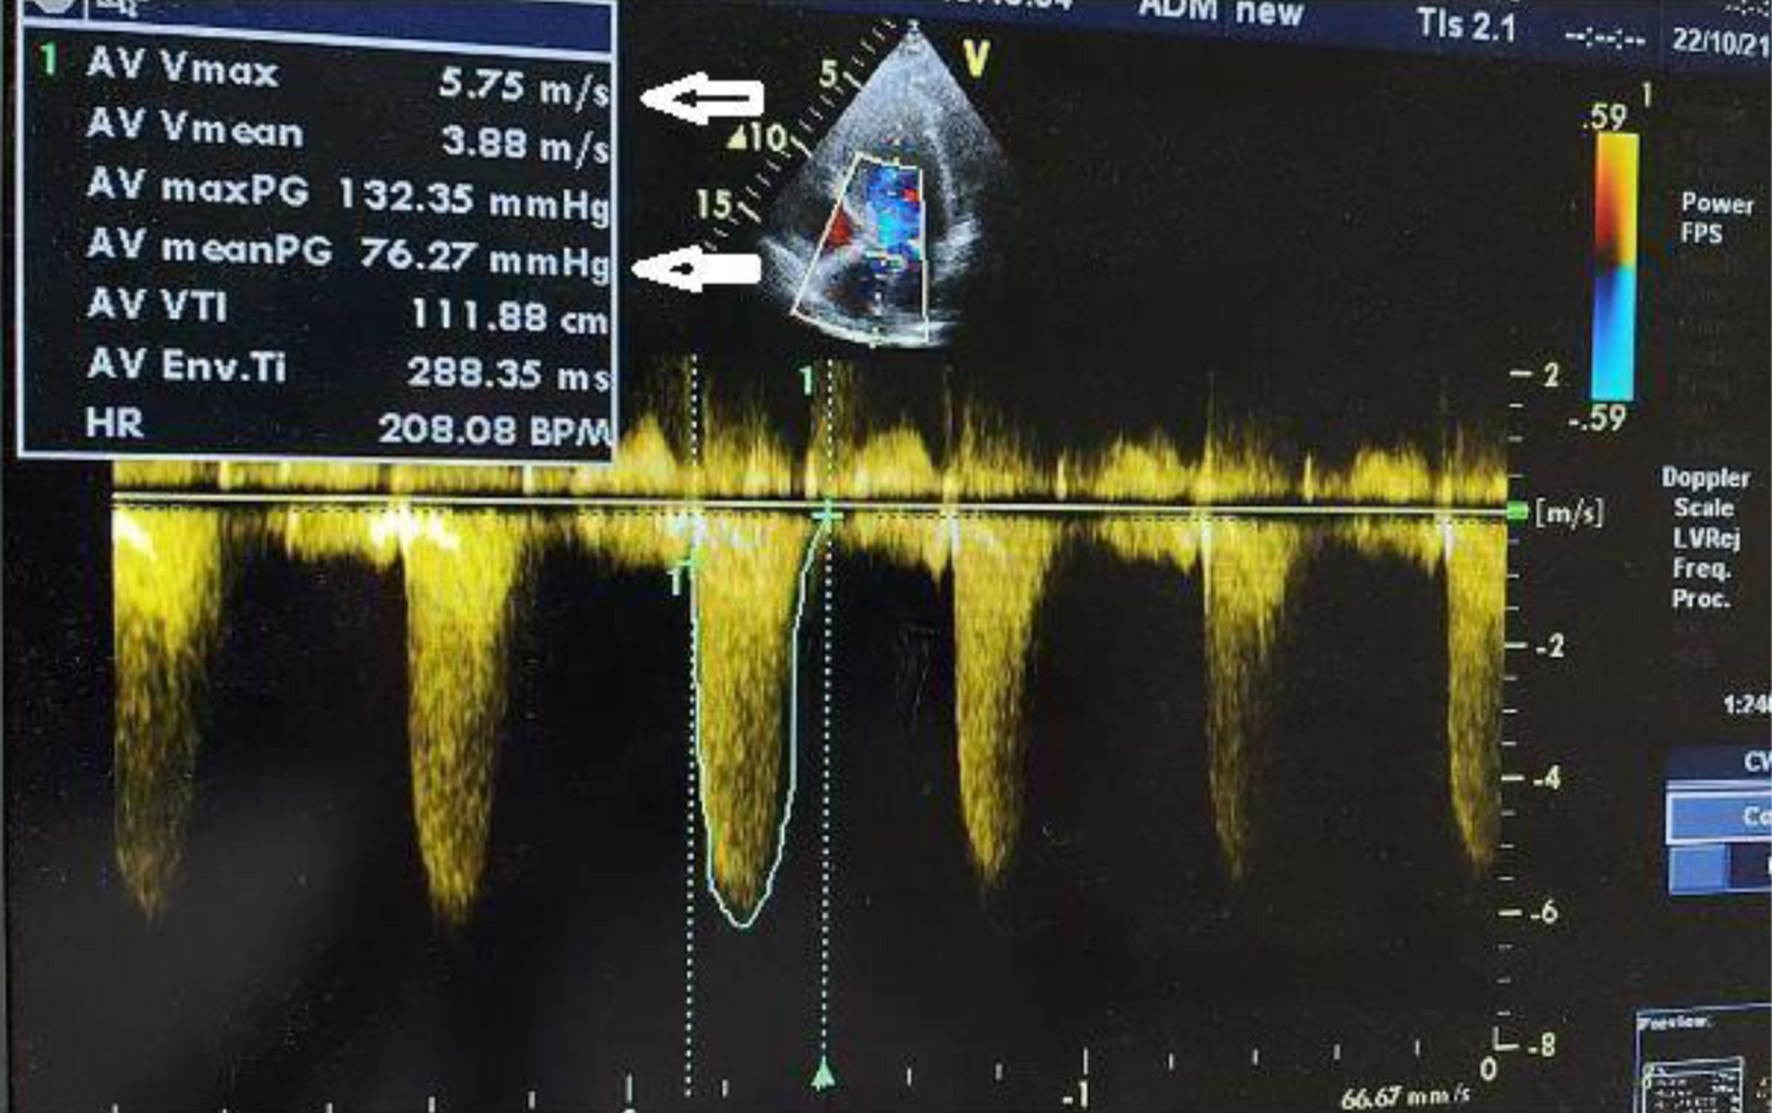

The patient, who had undergone a left nephroureterectomy 1 year earlier for urothelial carcinoma, presented again with suspected malignancy of the right upper urinary tract. Following urological consultation and instrumental evaluation (cystoscopy), urinary bladder tumors were detected, and the patient proceeded to further imaging assessment. Magnetic resonance imaging (MRI) of the upper abdomen revealed a tumor in the right kidney with invasion of the ureter and perirenal adipose tissue (Figs. 6 and 7). Lower abdominal MRI examination confirmed urinary bladder tumors with infiltration of the distal ureter and uterus (Figs. 811). Considering the patient’s clinical status, the potential aggressiveness of the malignancy, the absence of definitive histopathological confirmation of the new tumors (which could represent distinct lesions requiring separate pathological sampling), and the patient’s preference, no preoperative neoadjuvant therapy was administered. Surgery was therefore the only available therapeutic option, to which the patient provided full informed consent, despite her high-risk clinical profile and the complexity of the proposed high-risk surgical procedure. The postoperative histopathological report demonstrated high-grade renal urothelial carcinoma with contiguous extension to the ureter, urinary bladder, and bladder neck. Five of the 11 excised lymph nodes were metastatic, classifying the tumor as pT4N2Mx. Despite radiological evidence suggestive of uterine involvement, histopathological examination of the uterus and ovaries showed no malignancy; instead, polypoid endometrial hyperplasia and ovarian cysts were identified.

Figure 6. Lower abdomen magnetic resonance imaging (MRI) examination demonstrated tumor invading ureter (arrow).

Figure 7. Upper abdomen magnetic resonance imaging (MRI) examination demonstrated tumor invading renal parenchyma (arrow).